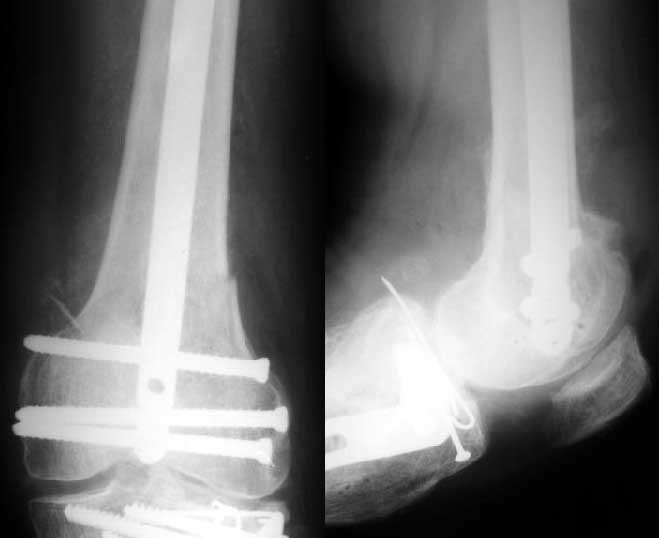

Отправитель: Alexander Chelnokov 27 Декабрь 2003, 21:34

1

Sorry but I've just prepared postop images - attached. A solid 13 mm nail was used. A few degrees of recurvation appears to be which i missed on image intensifier. I'm still uncertain about

advantages/disadvantages of ante/retrograde nailing for such fractures.

The fixation as you have done is excellent. The locking screws on either side of the # are so apart. When we put in a supracondylar nail thro a keyhole incison in the knee, the locking bolts will be nearer the # and will be more stable allowing him to bear wt early. That was the reason the supracondylar nail was innovated. The locking is done by jig and no freehand method saving time.